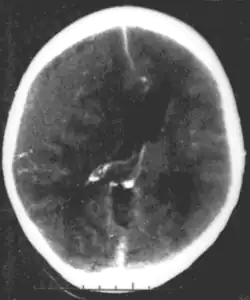

Epidural hematoma, an example of a focal injury

A focal traumatic injury results from direct mechanical forces (such as occur when the head strikes a windshield in a vehicle accident) and is usually associated with brain tissue damage visible to the naked eye.[3] A common cause of focal injury is penetrating head injury, in which the skull is perforated, as frequently occurs in auto accidents, blows, and gunshot wounds.[3] Focal injuries typically have symptoms that are related to the damaged area of the brain.[3] Stroke can produce focal damage that is associated with signs and symptoms that correspond to the part of the brain that was damaged.[1] For example, if a speech center of the brain such as Broca's area is damaged, problems with speech are common.